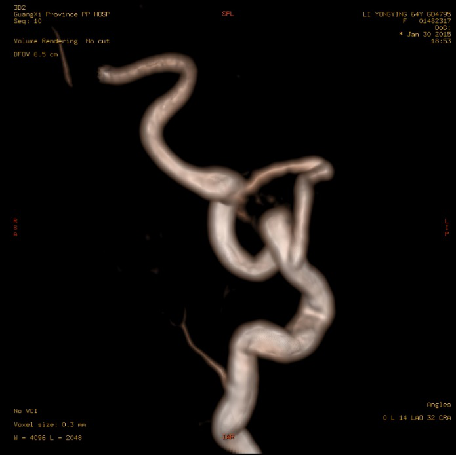

2015-1-30 DSA